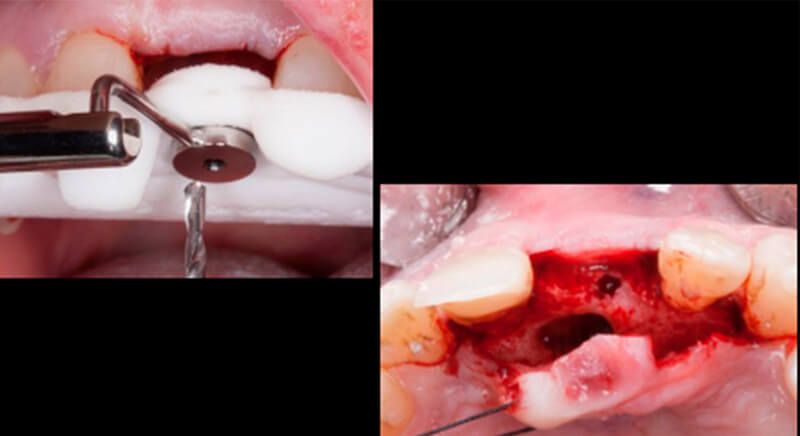

This information enabled us to rule out the option of surgery without a flap, as regeneration simultaneous to surgery would be needed, so the idea of using guided surgery was maintained.

The guided surgery was performed by lifting a full thickness mucoperiosteal flap. A Biomimetic Ocean CC implant, diameter 3.5mm and length 10mm, was inserted using the surgical guide in the ideal three-dimensional position and the defects were regenerated with xenograft and reabsorbable membrane, the nasopalatine duct on the palatine side and the area of dehiscence on the vestibular.